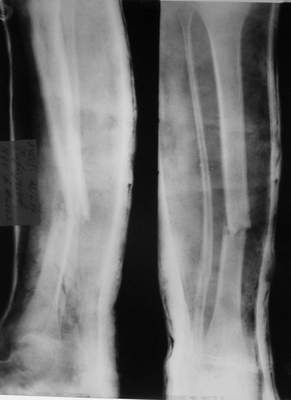

Перелом костей н\3 правой голени со смещением. Перелом большеберцовой кости можно охарактеризовать как компрессионно-оскольчатый.

Формирование некроза кожи по задней поверхности н\3 голени~ 1 %, вторичное заживление, кожная пластика. Нейропатия м\берцового нерва (отсутствие активного разгибания 1 пальца) На вытяжении около 8 нед, в дальнейшем в гипсовых повязках ~ 8 мес.

В январе 2005: варусная деформация н\3 голени, болевой с-м, комбинированная контрактура г\стопного сустава, нейропатия м\берцового нерва сохраняется слабость разгибания 1 пальца.

A> В январе 2005: варусная деформация н\3 голени,

а был у больного перелом дистального метафиза большеберцовой с чисто

варусным смещением на фоне пластической деформации малоберцовой на том

же уровне и того же характера.

Это сросшийся перелом малоберцовой кости. И ложный сустав

н\3 б\берцовой кости.